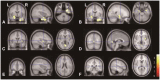

Results: In SPM8-based analyses, MTLE patients showed significant GMV reductions in the hippocampus ipsilateral to the epileptic focus, bilateral thalamus, and contralateral putamen in LMTLE patients. The GMV reductions were more extensive in the ipsilateral hippocampus, thalamus, caudate, putamen, uncus, insula, inferior temporal gyrus, middle occipital gyrus, cerebellum, and paracentral lobule in RMTLE patients. These patients also exhibited notable reductions of GMV in the contralateral hippocampus, thalamus, caudate, putamen, and inferior frontal gyrus. We observed that GMV reduction was positively correlated with several clinical features (epilepsy duration and seizure frequency in RMTLE, and history of febrile seizure in LMTLE) and negatively correlated with seizure onset age in both the RMTLE and LMTLE groups.

Conclusions: Our study revealed GMV decreases in the hippocampus and extrahippocampal regions. Furthermore, the GMV reduction was more extensive in the RMTLE group than in the LMTLE group, since it included the contralateral hemisphere in the former. This difference in the GMV reduction patterns between LMTLE and RMTLE may be related to a longer epilepsy duration and higher seizure frequency in the latter.